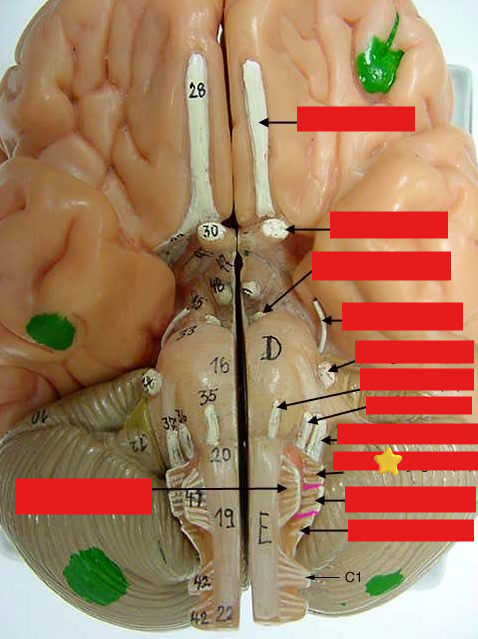

cranial nerves

12 Terms

1

olfactory

2

optic

3

oculomotor

4

trochlear

5

trigeminal

6

abucens

New cards

7

facial

8

vestibulocochlear

New cards

9

glossopharyngeal

New cards

10

vagus

New cards

11

accessory

New cards

12

hypoglossal

New cards